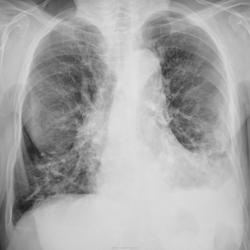

С подозрением на пневмонию направлена на рентгенографию ОГК.

Честно говоря, свежей инфильтрации не вижу. Легкие фиброзны, слева передне-базальные синусы облитерированы.

Возраст большой. Изменения сосудов в виде варикозных расширений, фиброз. В левом лёгком ,наверное, изменения в виде фиброза за счёт мелких тромбоэмболий. С сердцем проблем нет?

Согласна с фиброзными изменеиями и усиленным с/рисунком, структура корней нечеткая. И видится мне над куполом слева (в прямой проекции на фоне сердечной тени) газовый пузырь. Дала бы глоток бария.